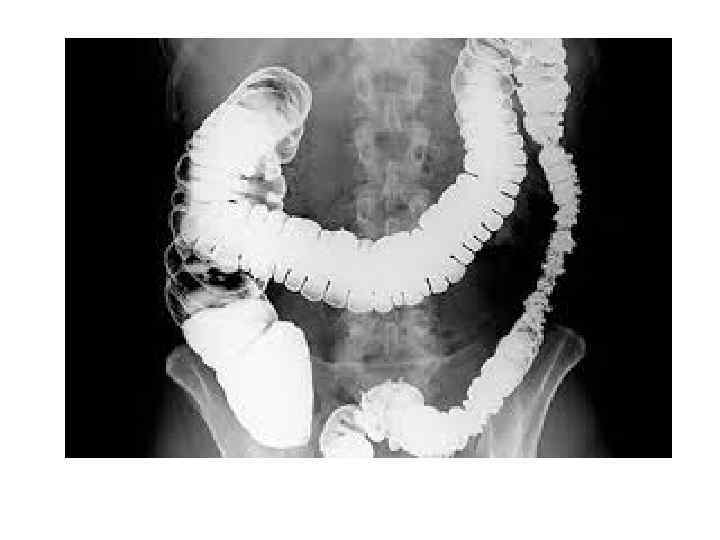

• Рентгенография брюшной полости: определение газа и уровней жидкости в петлях кишок (чаши Клойбера) поперечная исчерченность кишки (симптом керкринговых складок) • УЗИ: • при механической кишечной непроходимости: расширение просвета кишки более 2 см с наличием феномена «секвестрации жидкости» в просвет кишки; утолщение стенки тонкой кишки более 4 мм; наличие возвратно поступательных движений химуса по кишке; увеличение высоты керкринговых складок более 5 мм; увеличение расстояния между керкринговыми складками более 5 мм; гиперпневматизация кишечника в приводящем отделе • при динамической кишечной непроходимости: отсутствие возвратно поступательных движений химуса по кишке; феномен секвестрации жидкости в просвет кишки; невыраженный рельеф керкринговых складок; гиперпневматизация кишечника во всех отделах